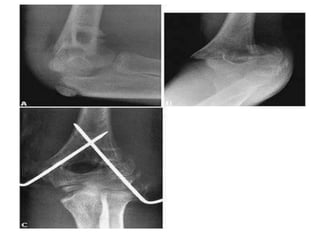

3/Skeletal traction –

-A stiff wire or pin is inserted usually behind the

tibial tubercle for hip, thigh and knee injuries, or

through the calcaneum for tibial fractures – and

cords tied to them for applying traction.